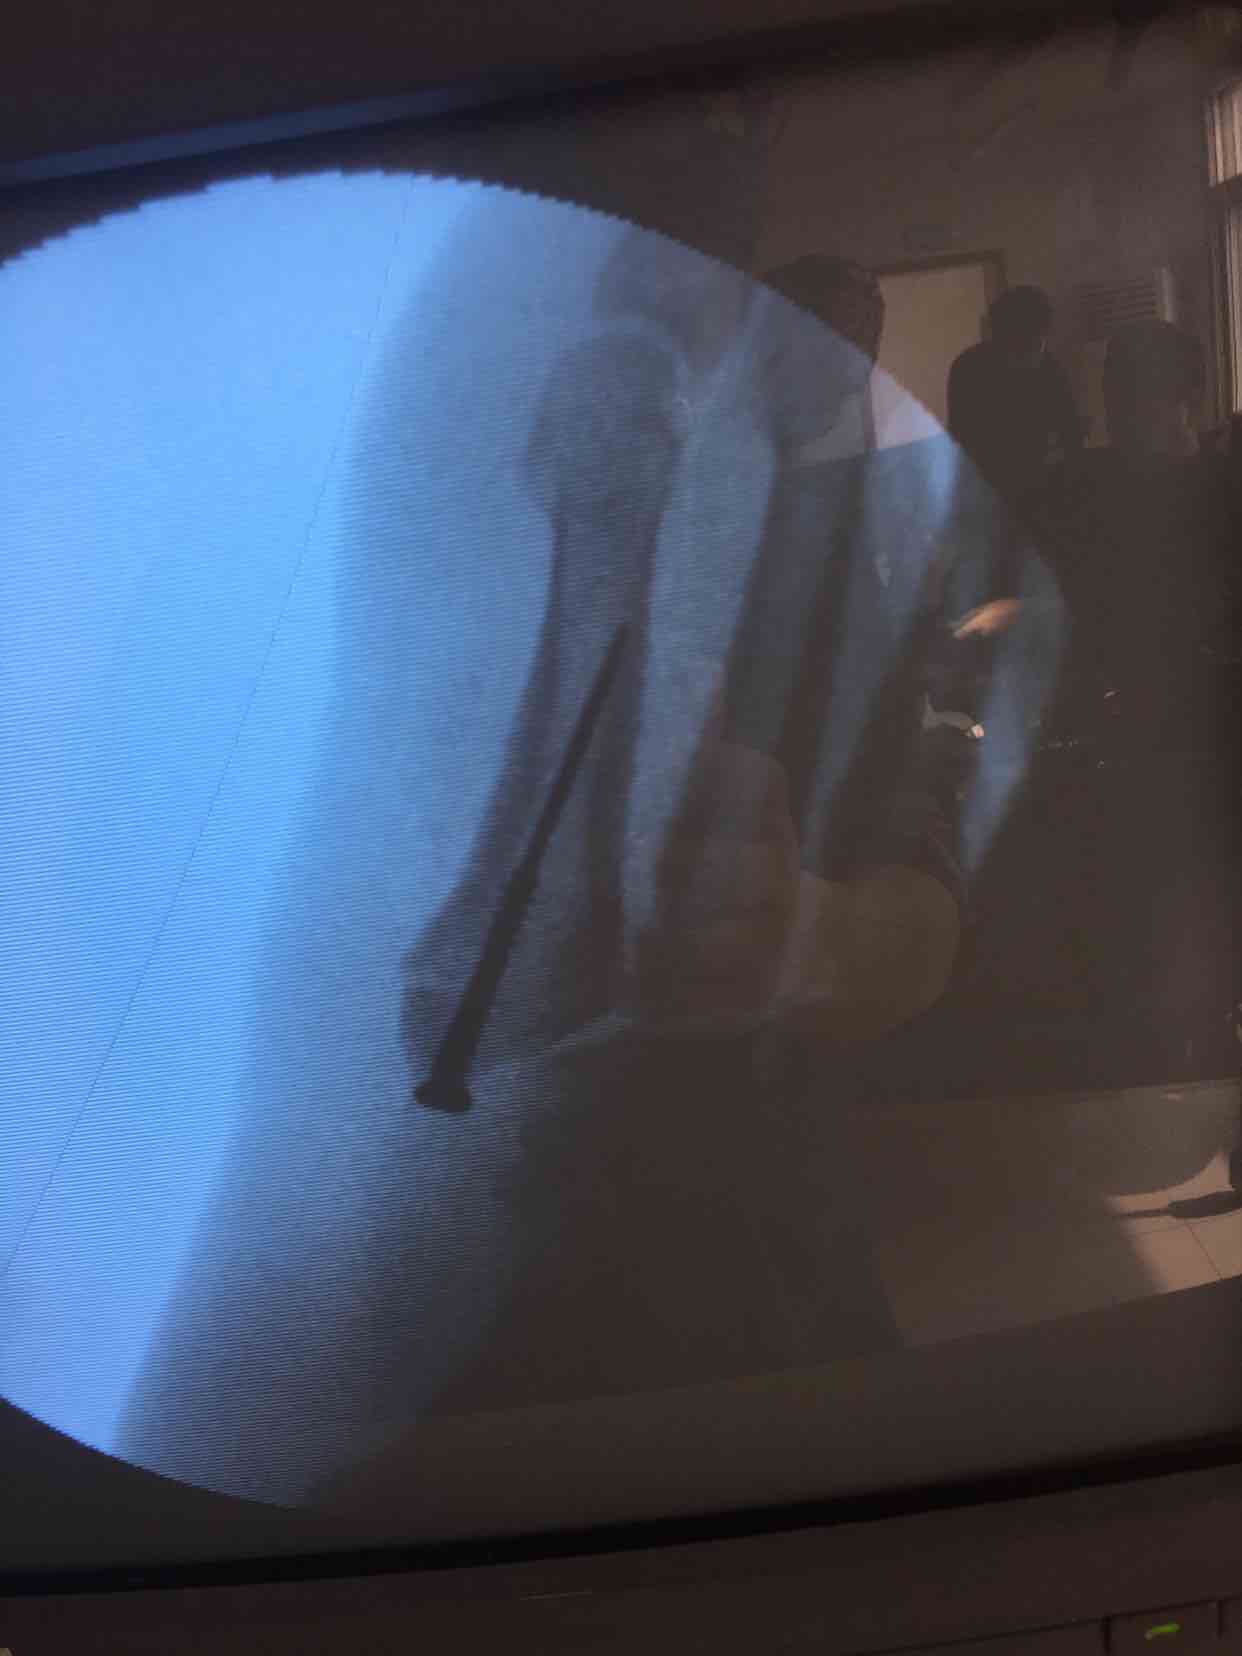

第五跖骨基底部骨折(切开复位内固定术)

摔伤后右足肿痛,活动受限16天入院。既往身体健康,无特殊不良嗜好。

心肺复未见异常,生命体征平稳。右足肿胀基本消退,局部皮色皮温基本正常,压痛及纵叩痛阳性,末梢血运感觉基本正常。

诊断第五跖骨基底部骨折(右)完善术前检查,在腰麻下行切复内固定术,术后抗炎,消肿等对症处理。